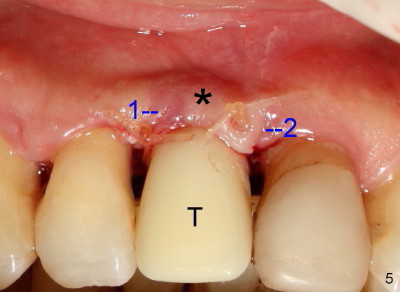

Fig.4-7 show modified semilunar incision helps form cosmetically-pleasing attached gingiva. Prior to uncover, the buccal plate of #8 (*) is concave, as compared to those of the neighboring teeth. The main incision is indicated by black line, lingual to the crest so that the buccal flap is more bulky. It is curved and festooned to create the future cosmetic buccal gingival margin. If the main incision is placed too lingual to expose the implant, one or two accessory incisions (red) can be made. After insertion of 4x6.5 mm non-shouldered abutment 3 mm post, PVS impression is taken. Fig.5 shows temporary crown in place (T) with two vertical mattress suture in the mesial and distal papillae. Two accessory incisions are approximated. The attached gingiva over the temporary crown immediately becomes bulky (*). Two weeks later, the temporary crown is removed. The accessory incision #1 has healed, while #2 is healing (Fig.6). The temporary crown helps form a nice socket around the abutment (A). The buccal attached gingiva (*) is leveling with that of the neighboring teeth, as compared to concavity before uncover (Fig.4). Fig.7 shows the gingiva around the crown (to be cemented) with healing incision #2. The buccal attached gingiva(*) is as bulky as immediately after uncover (Fig.5). Return to original article